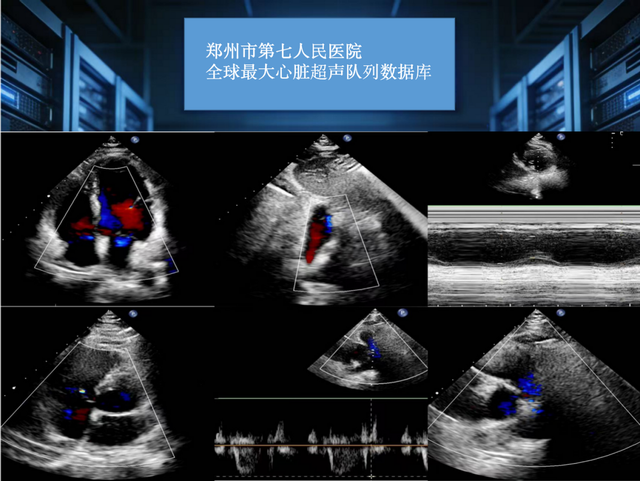

依托15万例真实临床患者数据支撑,聚焦心血管病理影像智能化解析与结构化报告输出,全球最大队列心脏超声报告生成大模型近日在郑州正式建成。这一重大医工交叉科研成果的落地,标志着郑州市第七人民医院在心血管影像多模态大模型研发应用领域跻身全球领先行列,为心脏超声诊疗智能化、同质化发展提供了硬核支撑。

为攻克这一痛点,郑州市第七人民医院心脏超声大模型课题组依托院内全球规模最大、标签体系完整的心脏超声大数据库,创新研发全流程自动化集成系统。目前,该系统已完成核心技术攻坚,并通过首都医科大学附属北京安贞医院、广东省人民医院等全国六大权威医疗中心外部多中心验证测试,技术稳定性、场景适配性获得行业权威认可,核心技术优势凸显三大亮点。

多源影像阵列解析。系统具备超强数据处理能力,可高通量抓取、同步处理单次检查中数十帧核心切面数据,全面覆盖二维灰阶、彩色多普勒、组织多普勒等多类型影像,通过深度学习算法极速完成心脏解剖结构、运动轨迹特征精准提取,大幅提升影像解析效率。